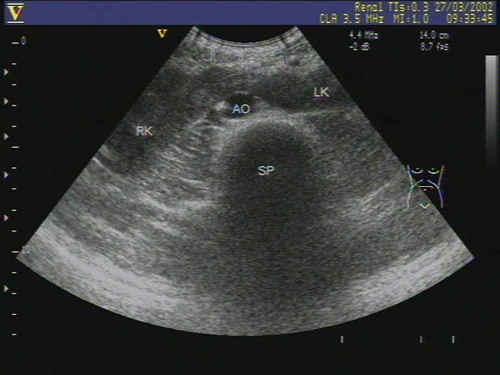

肾先天性反常--融合肾? - 超声医学讨论版 - 爱爱医医学论坛

图片尺寸640x480